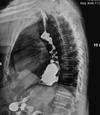

CXR: ARDS, exclude perforated DU